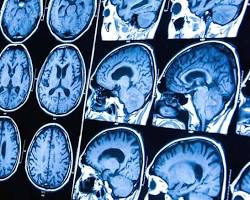

7. Cefaleia por tumor cerebral:

• Causa: Crescimento anormal de células no cérebro.

• Sintomas: Dor progressiva, geralmente piora ao acordar e com a tosse, pode ser acompanhada por náusea, vômito, alterações neurológicas e convulsões.

• Duração: Variável, depende do tipo e localização do tumor.

• Tratamento: Cirurgia, radioterapia, quimioterapia, analgésicos.